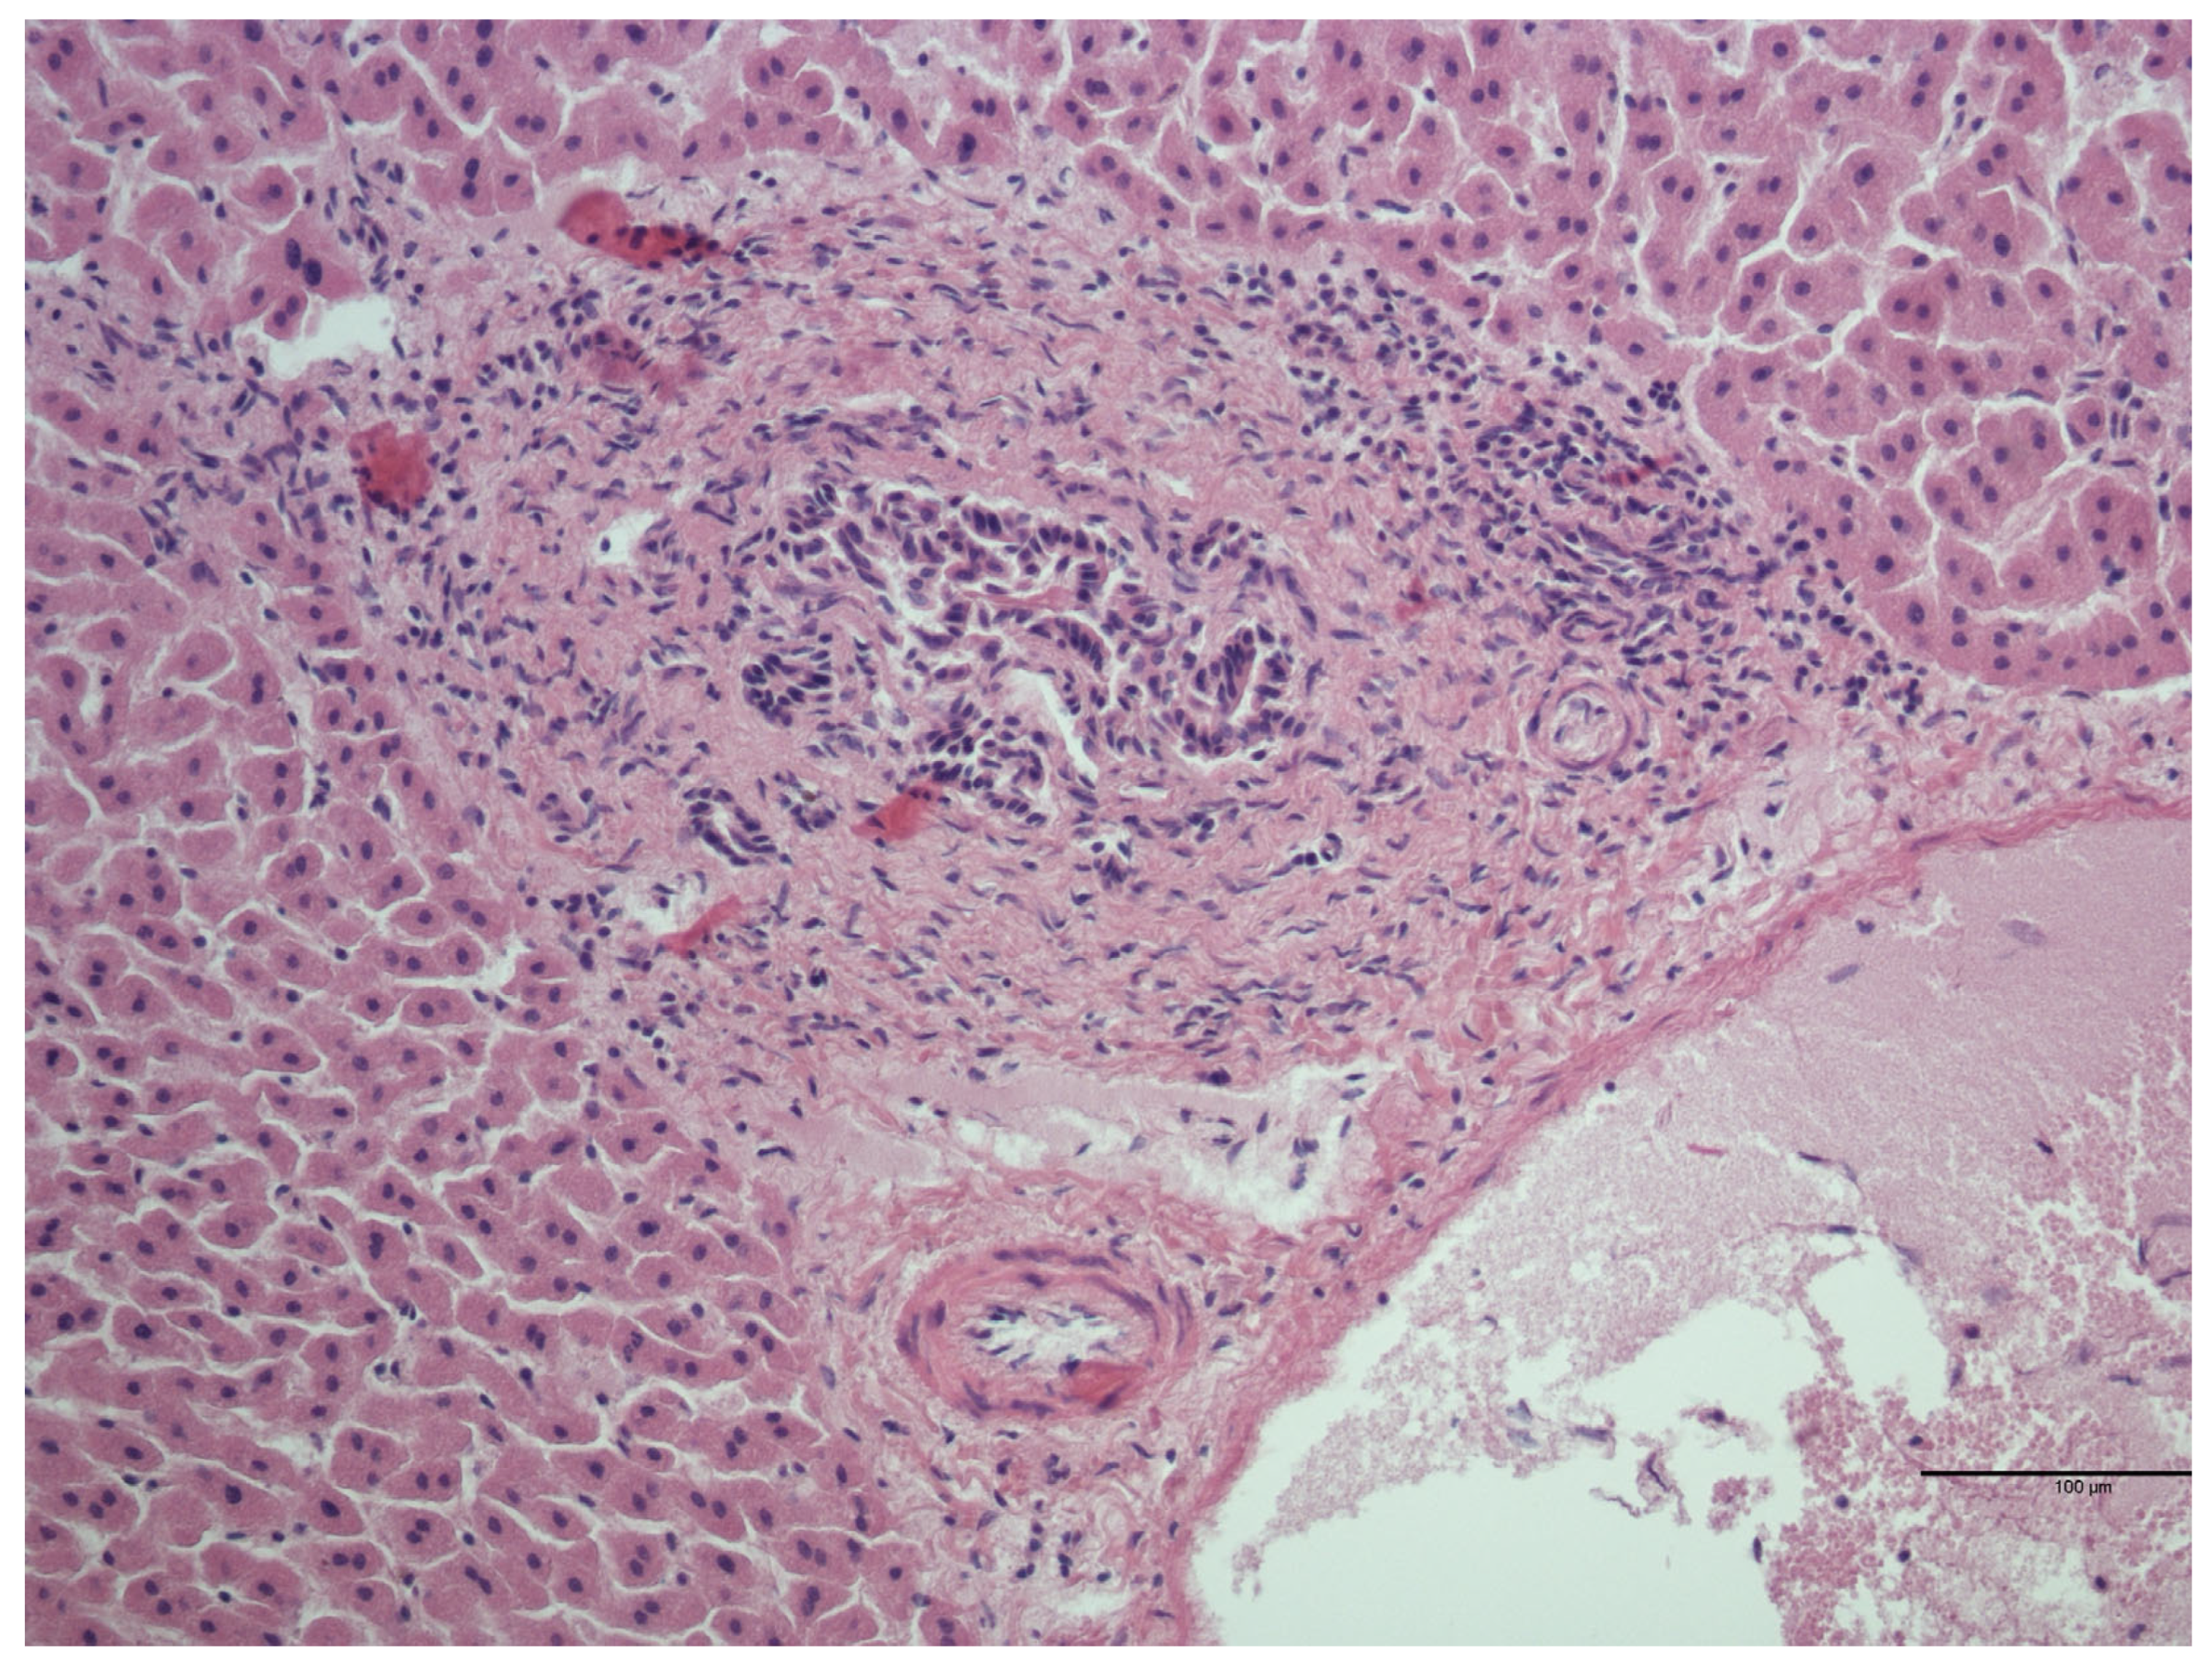

3.2. Histological Analysis

| Lesion | Number of Samples Positive for the Lesion/Total Number of Microscopical Lesions (%) |

|---|---|

| Interstitial lymphocytic nephritis | 20/23 (87.0%) |

| Urine crystals | 2/23 (8.7%) |

| Perivascular lymphocytic infiltrate | 1/23 (4.3%) |

| Cyst with focal lymphocytic infiltrate | 1/23 (4.3%) |

| Interstitial lymphocytic and eosinophilic nephritis | 1/23 (4.3%) |

| Lymphocytic infiltrate into perirenal fat | 1/23 (4.3%) |